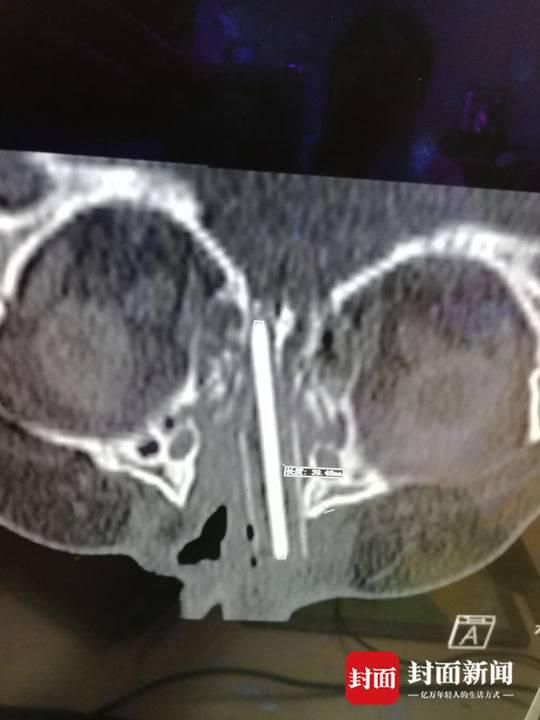

女童玩铅笔不慎戳进鼻腔 医生取出4.5cm残留部分

24日清晨,成都市妇女儿童中心医院耳鼻喉科主任、主任医师徐幼醒来后的第一个电话打给了病房,询问昨天接受手术的小患者的情况。这个2岁的广西小女孩彤彤(化名)在玩耍时,不慎将铅笔戳进鼻腔直达鼻颅底,再深一点伤到颅底后果不堪设想。

好在手术顺利,现在恢复的情况也不错。徐幼提醒家长,尽量不要把铅笔、筷子、树枝等尖锐的东西拿给孩子玩耍,避免造成意外。